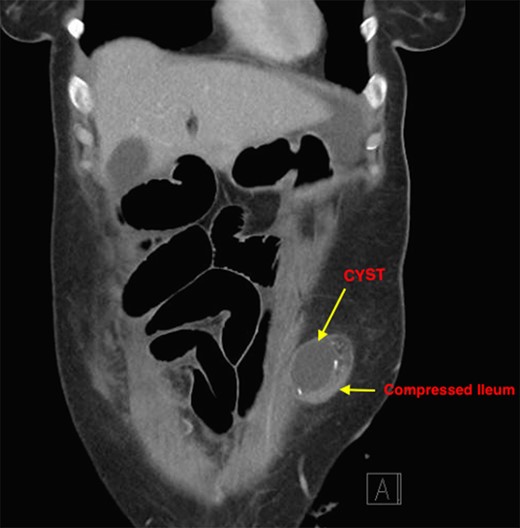

The patient recovered well with the stoma functioning well until Day 6, when she developed a small bowel obstruction. CT scan demonstrated cystic structure compressing the ileum loop within the anterior abdominal loop just before the stoma opening (Figs 1 and 2). Digital stomal examination and Foley’s catheter failed to pass through the stoma opening confirming the obstruction being at the abdominal wall. Failure of supportive measures, the patient was taken to theatre for revision of the stoma. Per stoma endoscopy was attempted with a gastroscope and which also failed to traverse the compression. At surgery, a semicircular skin incision was made adjacent to the stoma revealing what remained of the efferent ileal loop transformed into cystic mass abutting the stoma causing tight compression and was tightly adherent to the afferent ileal loop (Fig. 3). This was drained and partially excised with limited mobilization of the stoma. The remnant mucosa adherent to the afferent ileal loop was cauterized. Her recovery was unremarkable and was discharged Day 4 postsurgery. Histopathology of the partially excised cyst wall confirmed small bowel with viable mucosa showing mucosal flattening and complete loss of the villi.

Cross sectional CT Image showing compression of ileostomy opening.